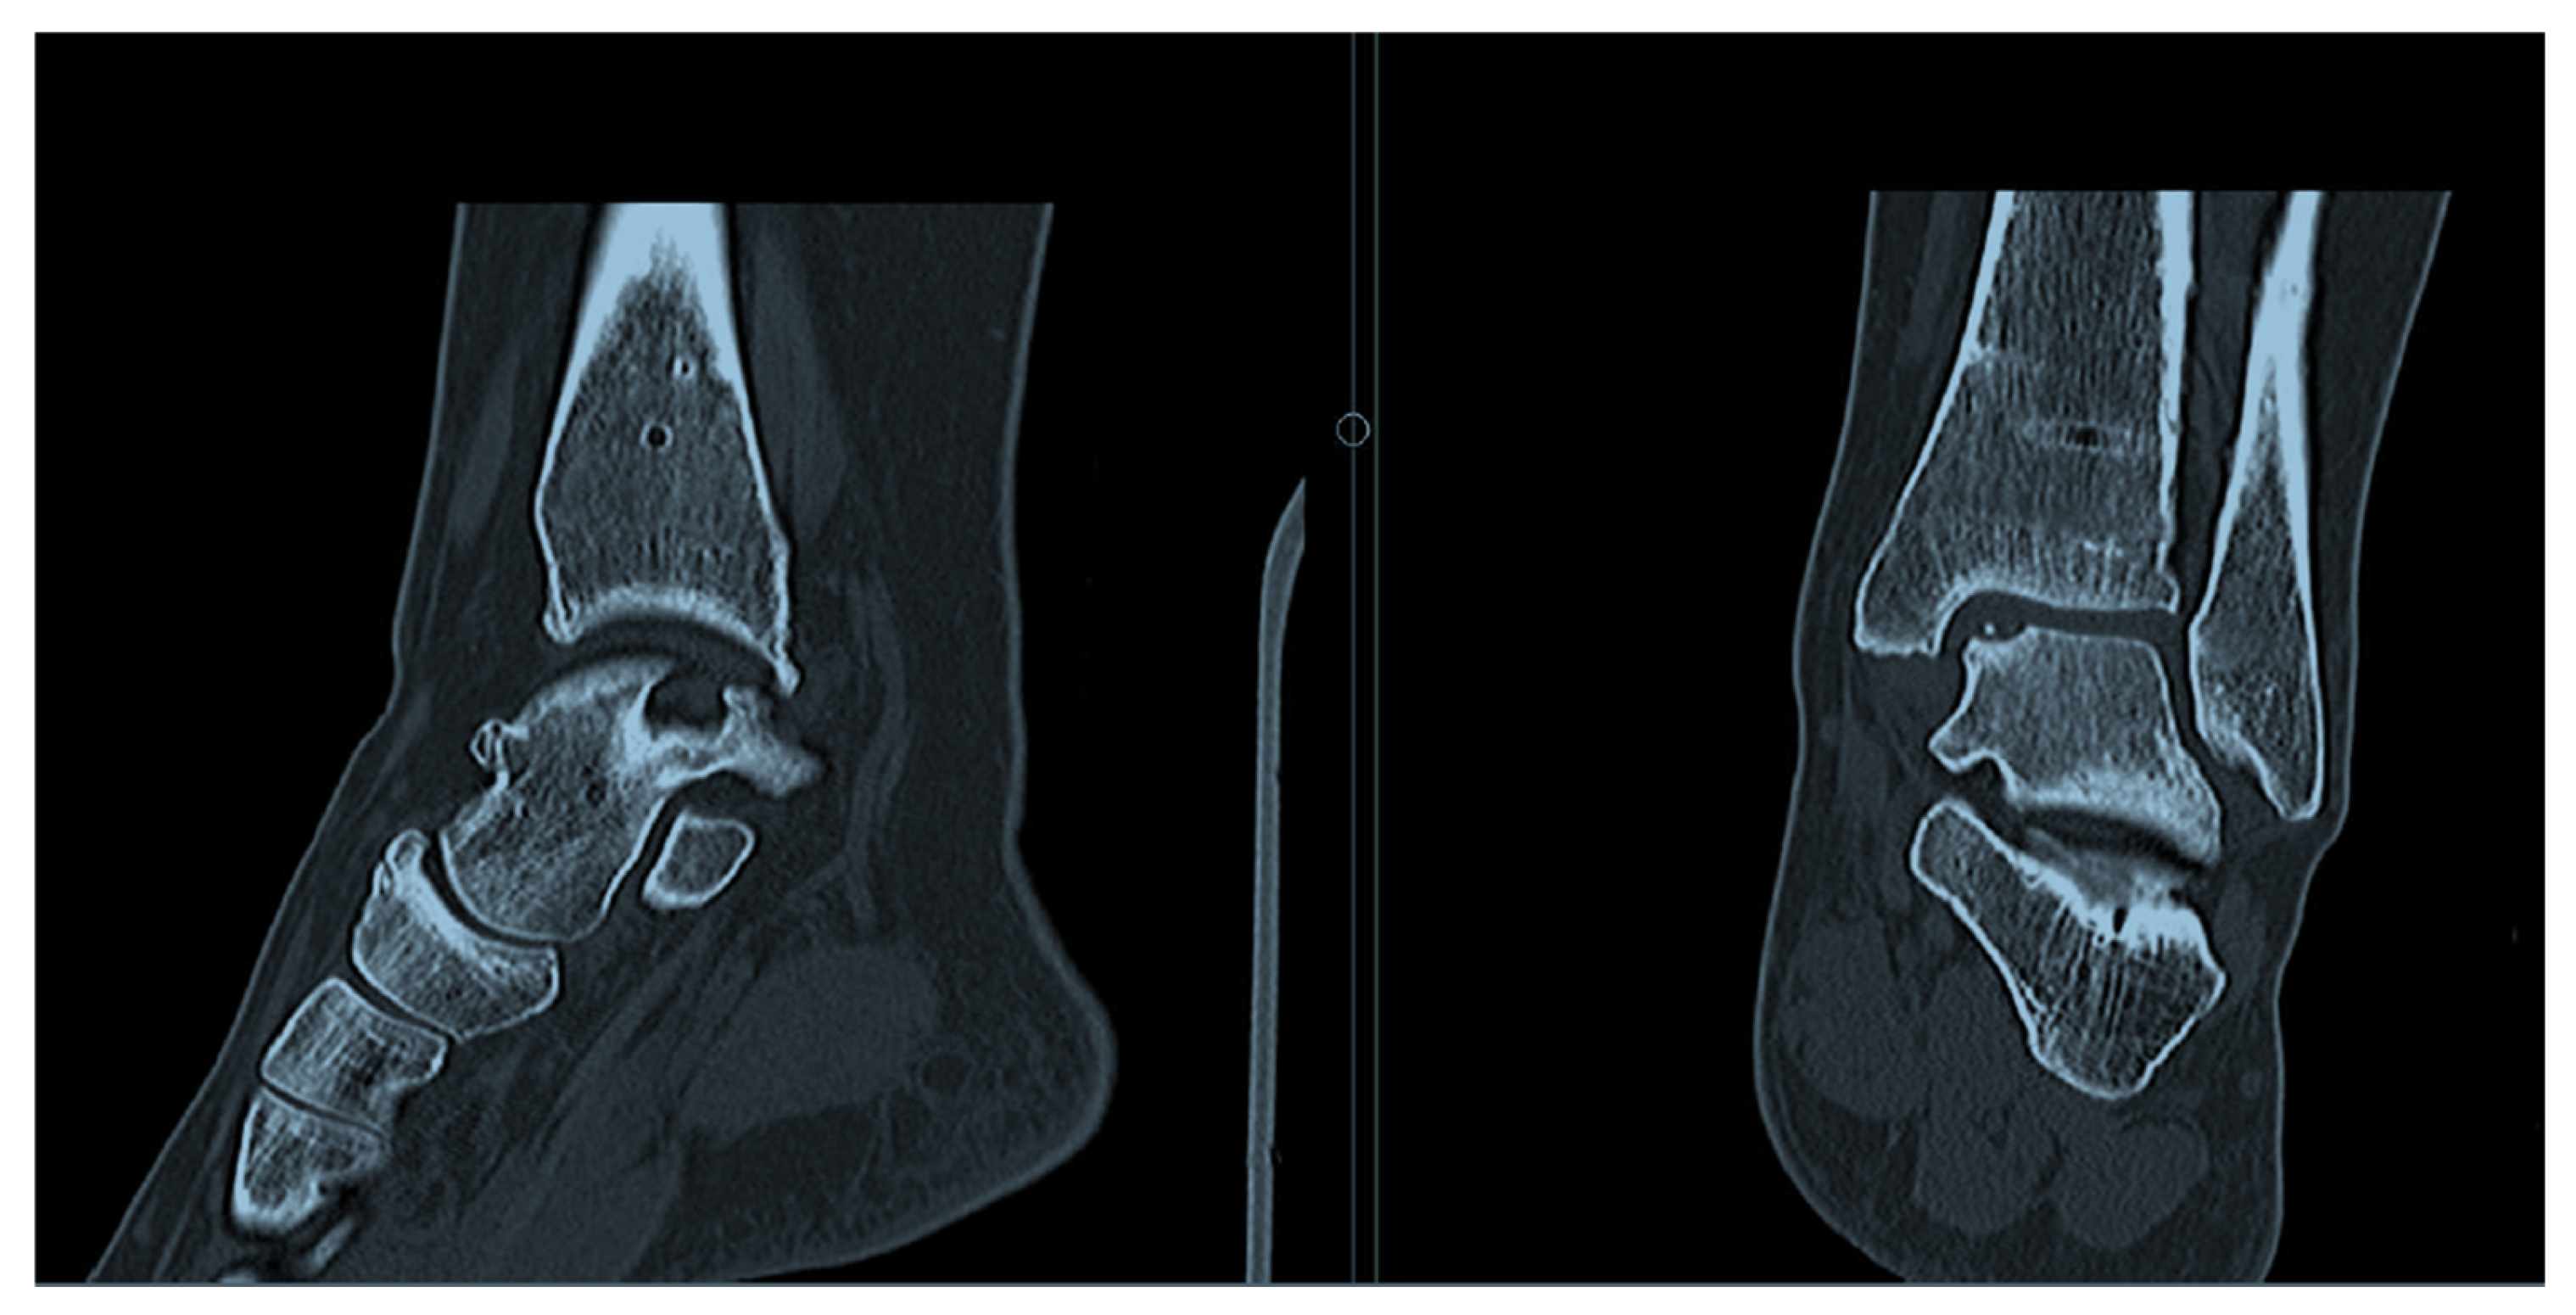

2.3. Radiological Assessment